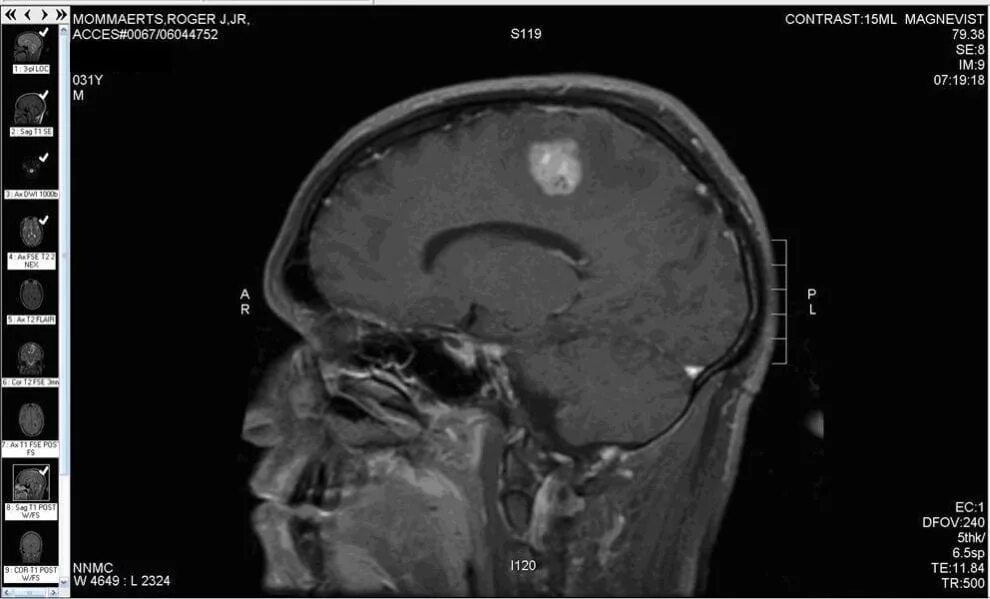

Как умирают от рака головного мозга